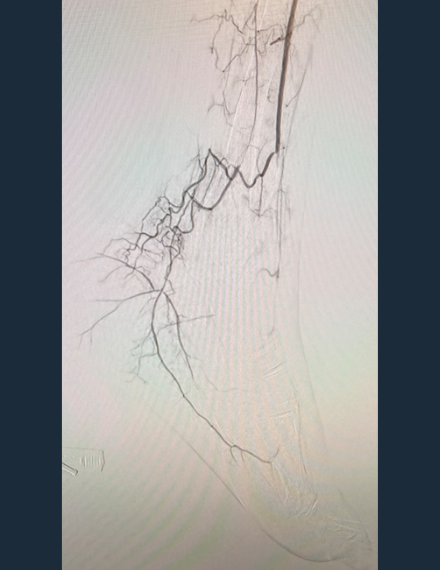

Pre-Procedure Angio

Occlusive calcium in AT extending into DP -